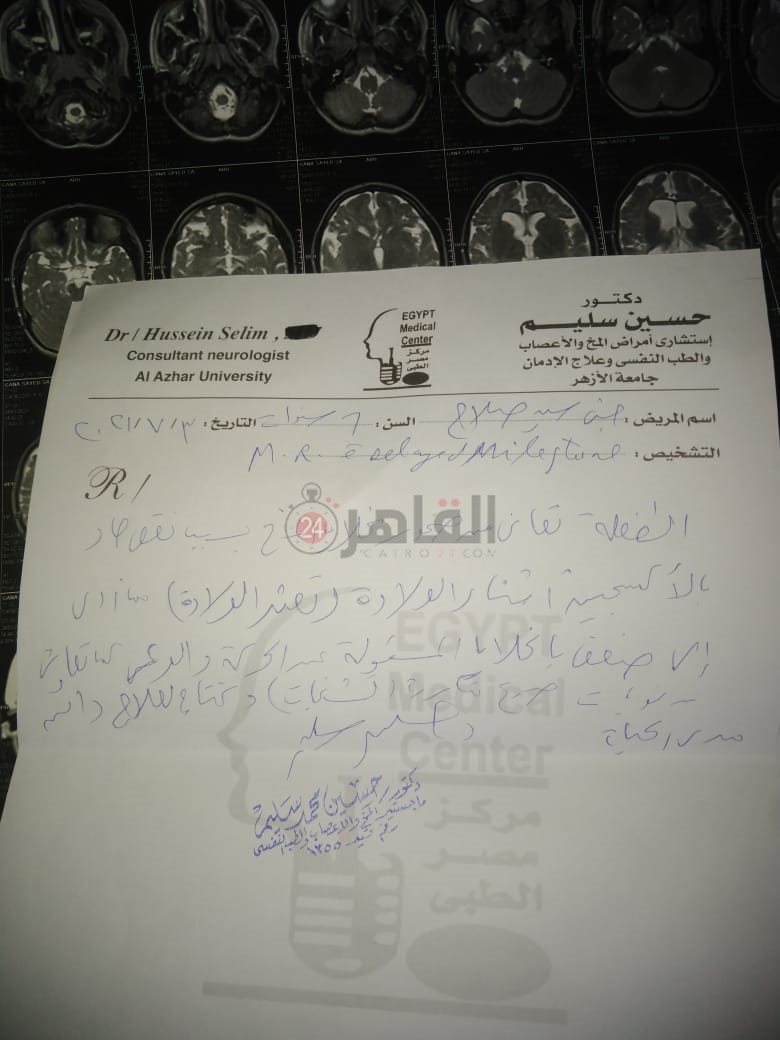

من جانبه، قال صلاح سيد، والد الطفلة جنى صلاح، إن ابنته تعاني من ضمور في المخ منذ ولادتها، نتيجة خطأ طبي، أدى إلى نقص كبير في الأكسجين لديها.

وأضاف في تصريحات خاصة لـ "القاهرة 24": "جنى تبلغ من العمر 6 سنوات، لا تستطيع المشي أو الوقوف على قدميها، نتيجة إصابتها بضمور في المخ منذ ولادتها".

وتابع: "مكنتش بتتحرك خالص، وجسمها طري، روحت كشفت عليها، وعملت أشعة وتحاليل كتير، أتأكدنا إصابتها بضمور في المخ"، مضيفًا:" مش بتعرف تأكل احنا اللي بنأكلها، هي عقلها كويس لكن مش بتتحرك ولا تتكلم".

وأوضح أن الطبيب الخاص بها أكد أن هناك داء خارج مصر يحسن من حالتها، ولكن باهظ الثمن، وتحتاج تناوله بشكل دوري.